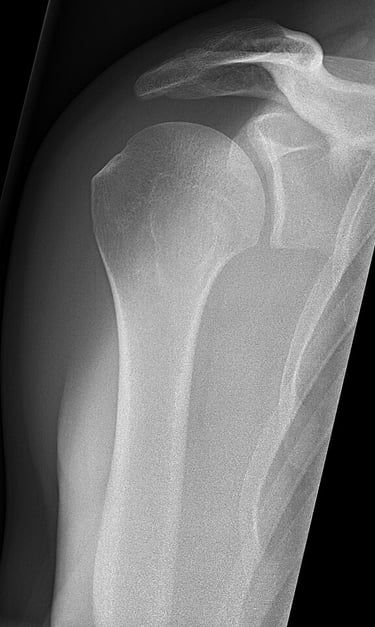

La inestabilidad de hombro aparece cuando la cabeza del húmero se desplaza parcial o totalmente fuera de su posición normal en la cavidad glenoidea de la escápula. Esta pérdida de congruencia durante el movimento puede deberse a una luxación previa, microtraumatismos repetidos o una laxitud articular generalizada.

La articulación del hombro está formada por la cabeza del húmero -que es esférica- y la cavidad glenoidea de la escápula -que es más pequeña y plana-, similar a una pelota de golf sobre su base. Esto otorga una gran movilidad al complejo del hombro en diferentes planos, pero le resta estabilidad a la hora de controlar ese movimiento.

Para reforzar esa estabilidad tenemos elementos activos: músculos y tendones, y elementos pasivos: ligamentos, cápsula y rodete articular del labrum. El fallo de alguno de estos elementos puede dar lugar a un hombro inestable.